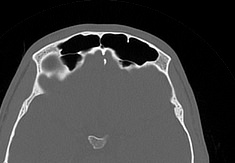

Лицевой череп состоит из крупных костей (верхняя и нижняя челюсти, лобные кости, скуловые кости) и сгруппированных вокруг них остальных мелких костей. При травмах лицевых костей часто наблюдается смещение мелких отломков, которые не видны при обычной рентгенографии. Мультиспиральная компьютерная томография позволяет детально изучить кости лицевого черепа, а также углубления, которые являются вместилищем для важных органов (глазницы, полость носа, ротовая полость).

Метод КТ основан на применении рентгеновского излучения и различной способности тканей поглощать рентгеновские лучи. Костные структуры обладают наибольшей плотностью по сравнению с другими тканями, поэтому в большей степени поглощают рентгеновские лучи и лучше всего визуализируются при данном исследовании.

КТ костей лица является наиболее информативным методом диагностики травм лицевого черепа, посттравматических деформаций, аномалий развития, инородных предметов в носовой полости и околоносовых пазухах. Кроме того, мультиспиральная КТ применяется при воспалительных заболеваниях ЛОР-органов, а также для выявления опухолевых образований доброкачественного и злокачественного характера.

Детальные изображения костей лицевого черепа получаются за счет вращения трубки томографа с излучателями рентгеновских лучей вокруг объекта исследования. В аппаратах увеличено количество сверхчувствительных детекторов, позволяющих производить множество послойных снимков с толщиной среза от 0,5 мм, которые затем преобразуются в трехмерные пространственные модели черепа. Такие инновационные возможности аппаратов обеспечивают проведение точной и достоверной диагностики.